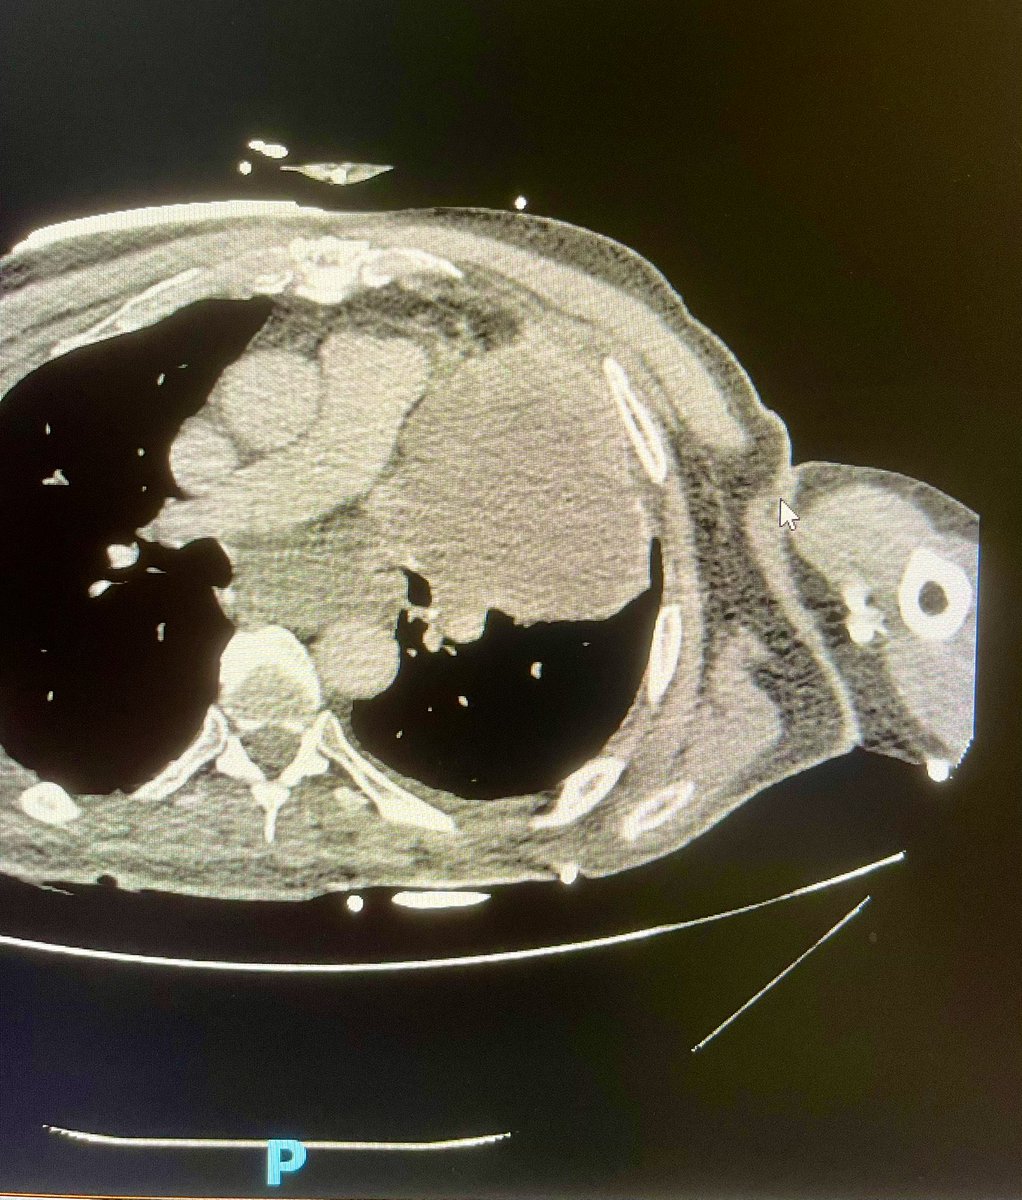

A 77 year old man with very large Left lung mass (10 cm) with this echo finding: CT shows large mass A3C: LV is hyper dynamic, chordal SAM LVOT CWD: dynamic gradient Q: why is dynamic gradient higher every 4th cardiac cycle? @ASE360 @OHSUCardFellows @iamritu @CASivaram1

That's correct. The mass moves with respiration pushing against LV, creating SAM and intermittent dynamic LVOT obstruction